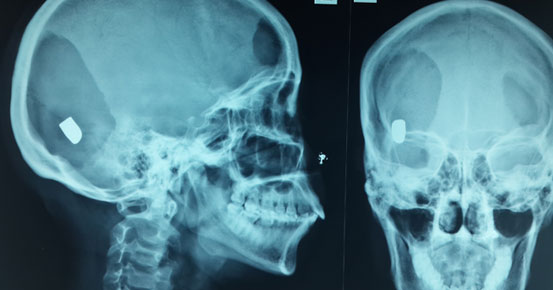

Egy pisztolylőszer lövedéke nagyon leegyszerűsítve olyan, mint egy fúrógép hegye: egy lyukat csinál, ha ez áthalad valami létfontosságún, akkor érvényesül valamiféle “kvázi-azonnali” KO hatás, ha nem, nem. A központi idegrendszert ért szolgálati kaliberű pisztoly találata (agyvelő, gerinccsatorna) ilyen. A szívet, fő verőereket ért találat pedig csak lehet ilyen. (A medencecsont összetörése is a támadó összeeséséhez, mozgásképtelenségéhez vezet – erre viszont a gyengébb pisztolylőszerek energiája, mélységi hatása elégtelen. Bővebben később. – A szerk.)

Mit is írtam korábban? A pisztolylövedék egy lyukat fúr a testbe, ha az valami fontosat ér, akkor van stophatás. Tehát kézenfekvő megoldás ennek az állandó sebcsatornának a növelése. Ezt megtehetjük a kaliber növelésével, vagy használhatunk expanzív lövedéket.